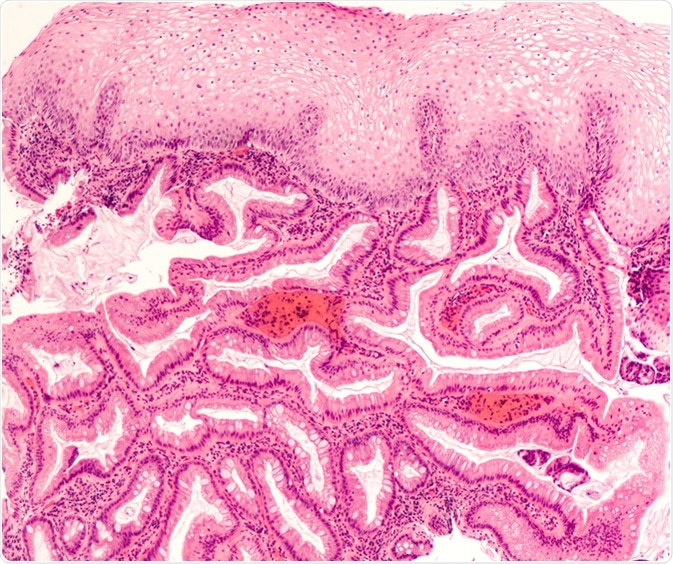

Intestinal (Barrett's) metaplasia of the esophagus is a response to injury from acid reflux (heartburn). It is associated with dysplasia and adenocarcinoma. Endoscopic biopsy photomicrograph. Image Credit: David Litman / Shutterstock